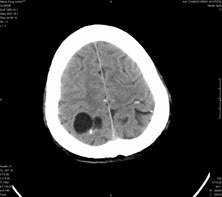

男,41岁,间断抽搐1小时,失神5分钟,bp130/90mmhg。低密度区ct值约16hu。

脑实质见多发散在的钙化点,左顶叶见一囊变灶,多考虑脑囊虫。

脑囊虫,部分囊内见头节。

脑实质见多发散在的钙化点,右颞、顶叶见囊性灶,考虑脑囊虫。

多发的囊泡(多发囊型)+多发的钙化(慢性钙化型)=混合型

顶叶最大的囊直径2.2cm,如果考虑囊虫的话,囊是不是有点儿太大了?